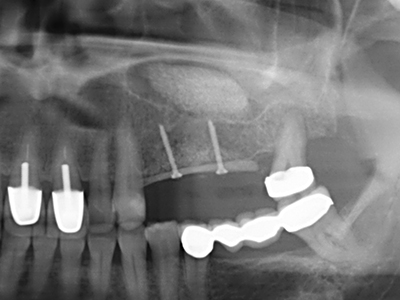

Aplicación: Preparación cerca del nervio

Si es preciso realizar intervenciones quirúrgicas en las que el hueso está en contacto directo con estructuras sensibles, como son los vasos sanguíneos o los nervios, los instrumentos rotativos presentan un enorme potencial de provocar lesiones iatrogénicas. Así, precisamente en la representación de nervios después de una lesión iatrogénica, o en el transcurso de la lateralización de un nervio para resecciones, reconstrucciones o incorporación de implantes, los equipos piezoeléctricos pueden resultar muy útiles para preparar la tapa ósea y retirar las partes de tejido duro cercanas al nervio (fig. 17-20). Por lo general, un ligero contacto del cordón nervioso con el inserto piezoeléctrico no tiene consecuencia alguna; ahora bien, un procedimiento poco cuidadoso con movimientos tipo sierra o piezas de trabajo sobre la base ósea aún existente puede provocar lesiones nerviosas temporales o incluso permanentes. Con todo, el riesgo de sufrir una lesión de este tipo se considera significativamente inferior que en los casos en los que se utilizan sierras y fresas (Pereira, Gealh et al. 2014).